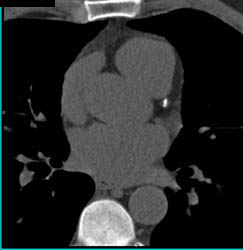

Plaque in LAD